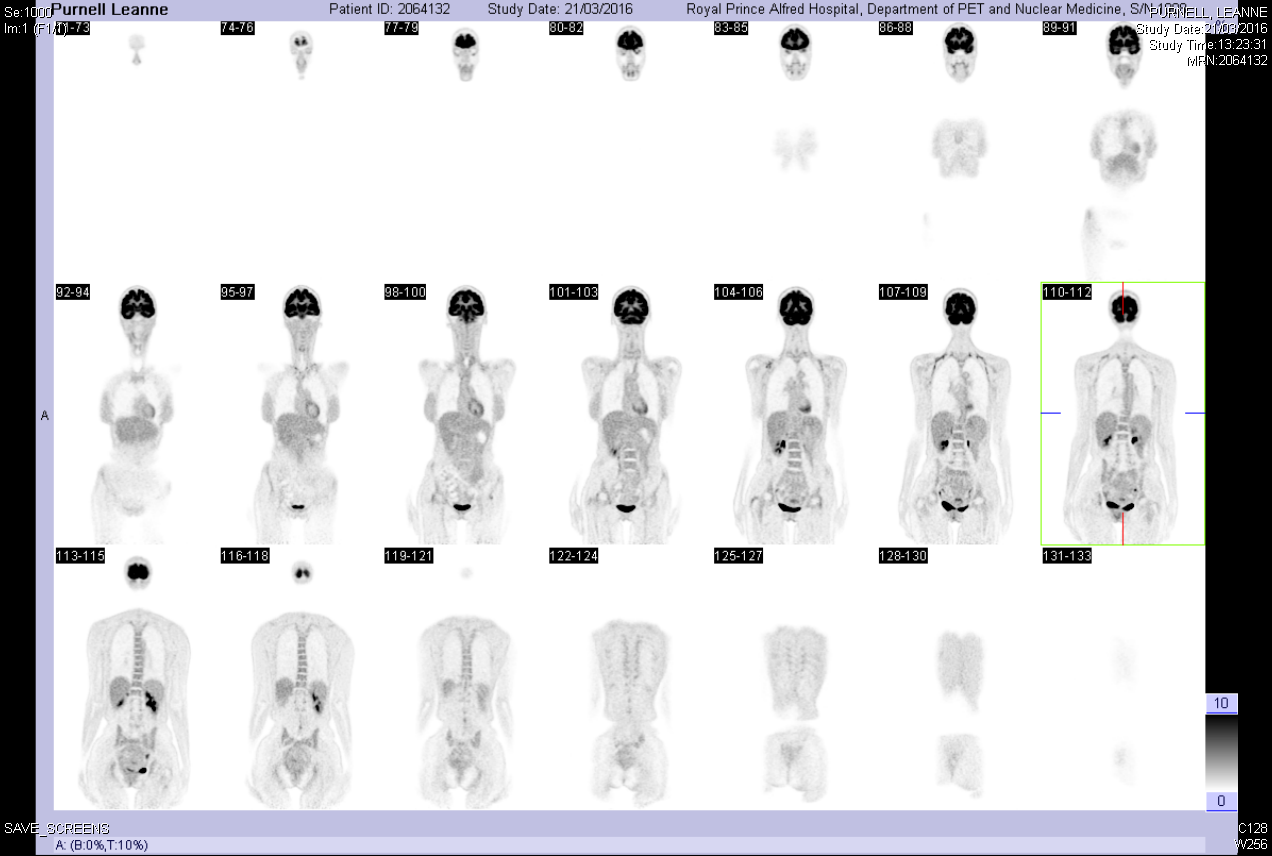

- VGCC antibodies positive – 281pM {< 30}

- 20 kg weight loss over the preceding 2 years

- No change in appetite, no night sweats

- CT CAP – NAD

- PET scan: